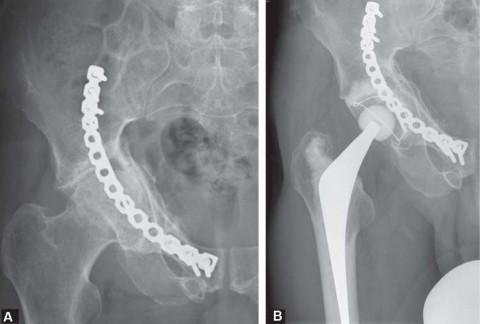

Introduction The basis of development of this chapter deals principally with the understanding of transtroc…